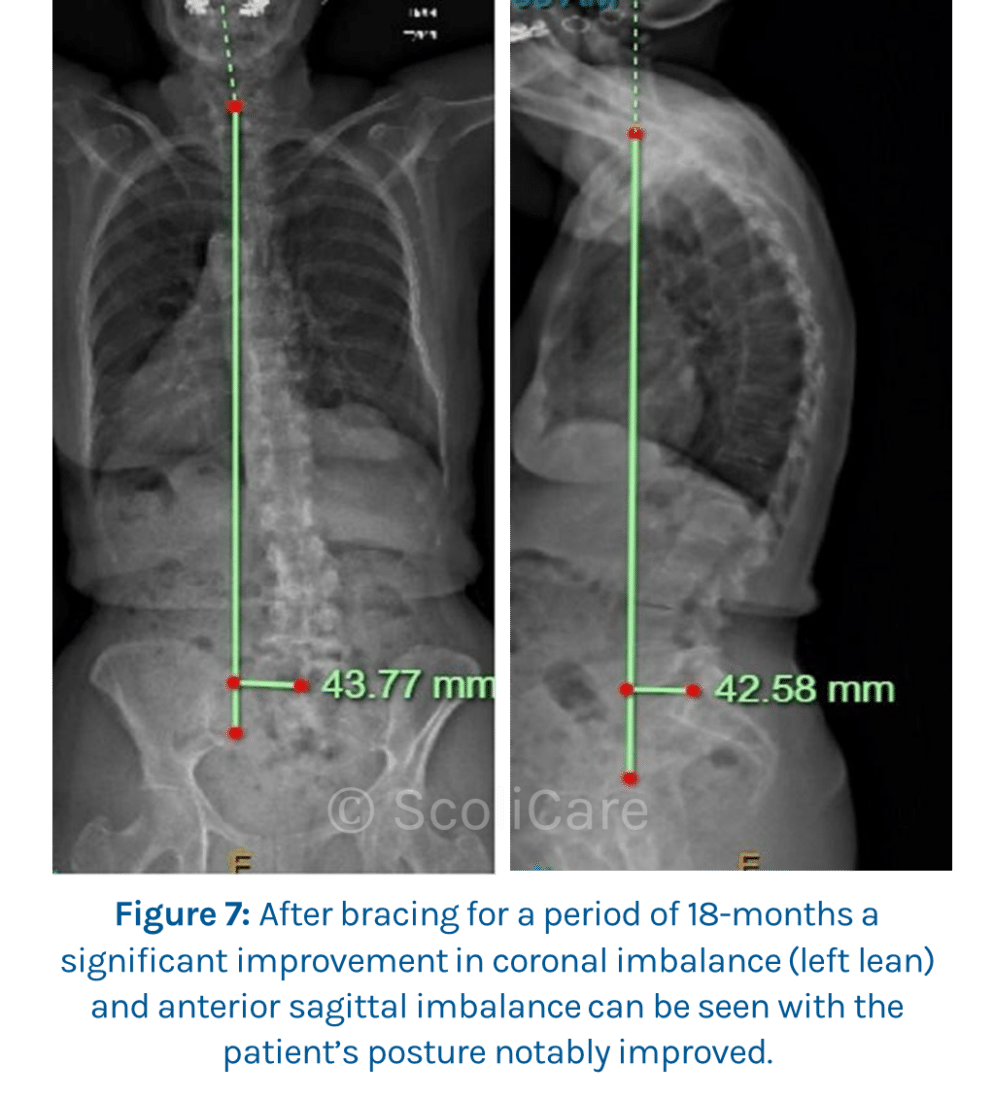

After wearing the brace for several hours, a day for a period of 18-months, a significant improvement in her coronal imbalance (left lean) by 21.34mm (32.77%), and anterior sagittal imbalance by 104.12mm (70.97%) can be seen (Figure 7). With the patient’s posture notably improved from the initial consult (Figure 8 and Figure 9) with wearing the brace for up to 8 to 10 hours per day.